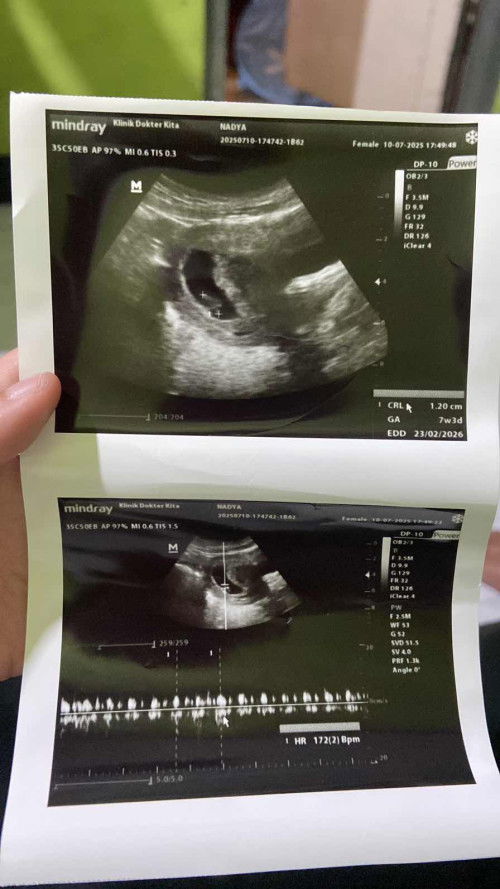

hai bunda semua aku mau tanya aku baru usg kmrn hpht aku kan 23 mei nah harusnya kemarin tuh masih 6 minggu 6 hari tapi di hasil usg udah 7 minggu 3 hari , tapi alhamdulillah janinya ada dan udah ada detak jantungnya aku diksih obat mual juga karena mual nya parah waktu pagi ini, aku jadi sering pipis tapi waktu pipis ada rasa perih setelah beres keluar air kencingnya dan ada darah sedikit dan ternyata di cd aku juga ada darah sedikit sedikit lagi kaya flek aman ga ya bun